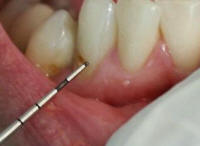

Sonda

Los límites de la superficie dental  deben ser conocidos para que el registro de la extensión de caries sea estandarizado